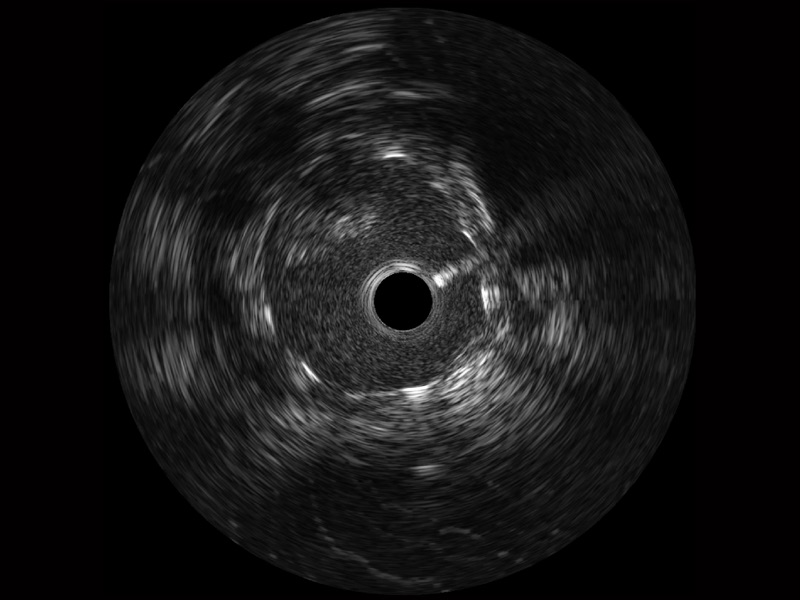

传统IVUS图像

对比传统IVUS导管成像,1xBET宽频IVUS图像的近场支架梁显影更细腻,远场中膜外血管仍清晰可辨,兼顾远中近,兼顾分辨力与穿透深度